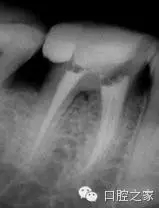

若干雜志均報道了近中牙根內(nèi)第三根管的存在。本篇系統(tǒng)性文獻回顧報道的是2.6%的第三根管發(fā)生率(圖2和3)。為了進一步定位第三根管,需要對開髓洞形進行改良。簡單地講,一旦定位了主根管,并對其進行根管預備后,使用小球鉆或超聲工作尖去除根管口間的牙本質(zhì)橋,為近中根的近中壁與髓腔形成的角提供了直視的視野,將兩個主根管間發(fā)育溝直接暴露出來。然后使用根管口探針探查根管,小號的根管銼順利的通暢根管。除此之外,手術(shù)顯微鏡的運用進一步提高了發(fā)現(xiàn)和治療副根管的可能性。還有一點必須要考慮的是近中根的遠中凹度,為了避免出現(xiàn)帶狀穿孔,第三個近中根管的預備過程要使用小號的根管銼謹慎小心的預備。中間近中根中根管完全獨立的患牙占整個病例中的25%。